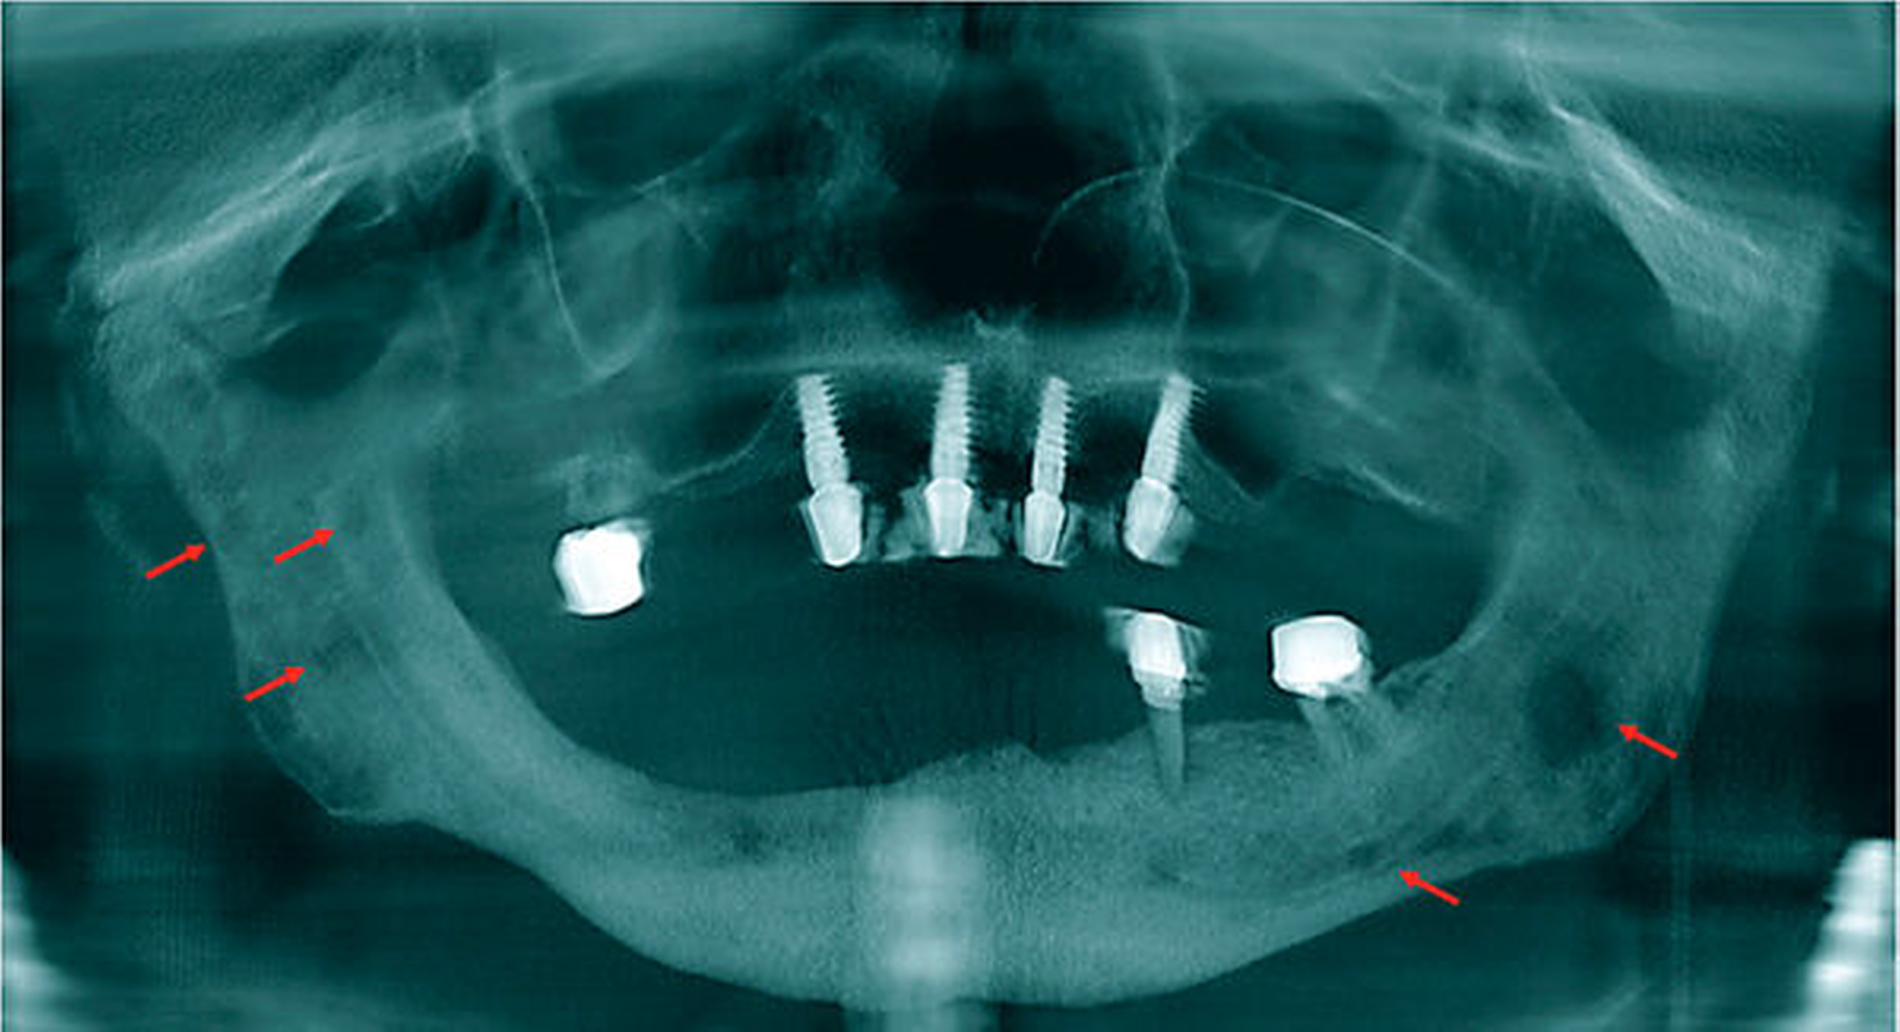

In der Panoramaansicht des aktuellen digitalen Volumentomogramms (DVT) zeigten sich osteolytische Läsionen des Unterkieferknochens sowie eine Minderung der vertikalen Knochenhöhe im vierten Quadranten bei Zustand nach modellierender Osteotomie.